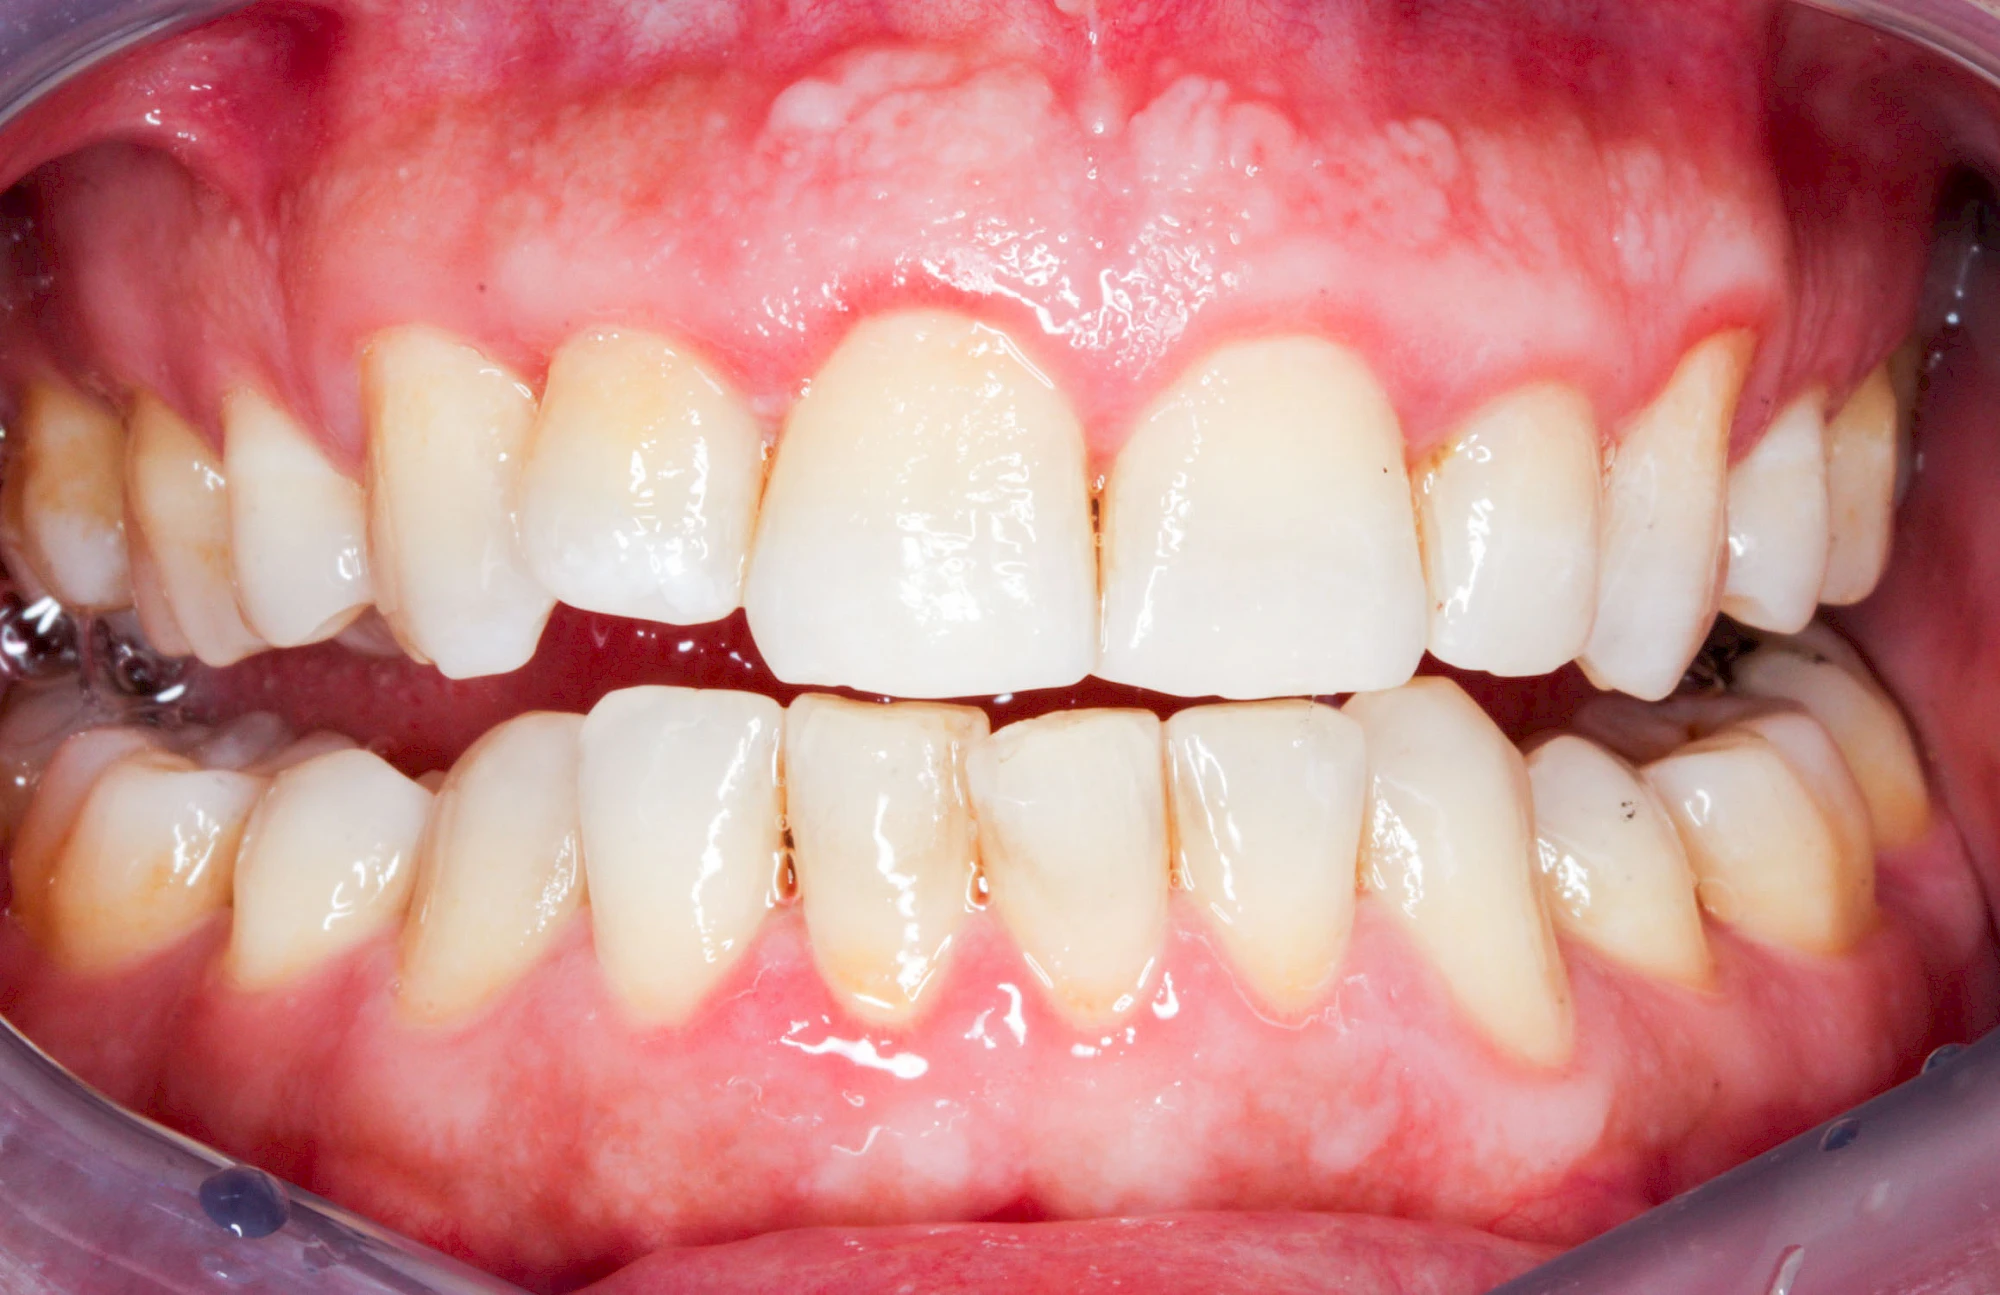

Bakterien in den Zahnbelägen greifen neben den Zähnen auch das Zahnfleisch (Gingiva) und den gesamten Zahnhalteapparat (Parodont) an. Der Körper reagiert mit einer Entzündung, sichtbar als Rötung und Schwellung. Meist blutet das Zahnfleisch z .B. beim Essen oder auch beim Putzen der Zähne.

Ist zunächst nur das Zahnfleisch von der Entzündung betroffen, spricht man von Gingivitis. Später, wenn auch der Knochen um die Zähne herum entzündet ist, spricht man von einer Parodontitis. Bei der Parodontitis wird der Knochen nach und nach abgebaut und das Zahnfleisch zieht sich zurück. Die Zahnhälse und Zahnwurzeloberflächen liegen mehr und mehr frei. Die Zähne werden zunehmend lockerer und fallen schließlich aus.